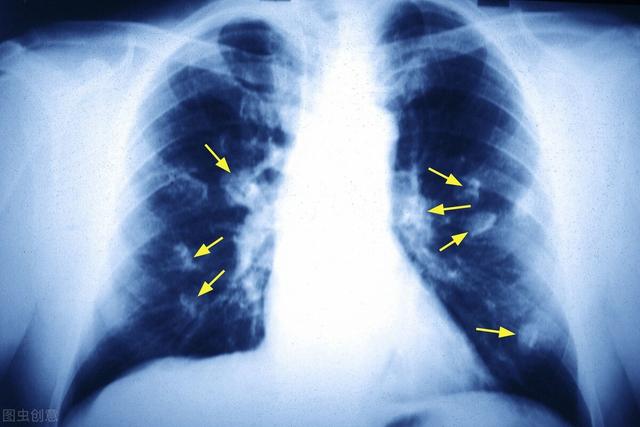

Lungenknoten werden in der Regel durch eine Röntgenaufnahme (Thoraxröntgen) oder eine Computertomographie (CT) entdeckt, vor allem durch die CT, denn viele kleine Knoten sind auf einem Thoraxröntgenbild überhaupt nicht sichtbar und müssen durch eine Computertomographie des Thorax entdeckt werden. Das ist es, was sich viele Menschen in den Schlagzeilen fragen, warum bei den jährlichen Vorsorgeuntersuchungen nichts zu beanstanden ist und man plötzlich Lungenkrebs bekommt. Es wird davon ausgegangen, dass die körperliche Untersuchung mit einem Röntgenbild der Brust und nicht mit einem CT durchgeführt wurde. Wenn man zum Beispiel sehen will, ob es wesentliche Läsionen (Wucherungen) in der Leber oder den Nieren gibt, muss man einen Ultraschall oder ein CT machen, und wenn man Magen-Darm-Läsionen sehen will, muss man eine Gastroskopie oder eine Koloskopie machen, nicht nur Labortests wie Blut- und Urintests, sondern auch Labortests für viele Läsionen, die normal sein können. Um kleine frühe Läsionen in der Lunge oder präkanzeröse Läsionen, vor allem Glasknötchen, aufzuspüren, wird eine niedrig dosierte Spiral-CT empfohlen.

Was ist zu tun, wenn Sie einen Lungenknoten finden??